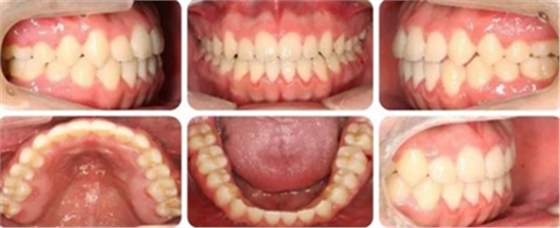

結(jié)束時,可見前牙覆合覆蓋正常,上下牙列排齊,雙側(cè)尖磨牙達到中性關(guān)系。

高角反頜伴開頜病例,多采用正畸正頜聯(lián)合治療。但該患者為直面型,下牙列輕度擁擠,下前牙直立,且年齡較小,手術(shù)治療非首選。采用種植釘內(nèi)收下前牙代償性治療前牙反合。而且需要拔除阻生智齒減小遠(yuǎn)移下牙列的阻力。

給患者帶來很大的負(fù)擔(dān)。而本病例通過下頜頰棚區(qū)植入微種植釘,整體將下頜牙列內(nèi)收,引起下頜骨逆時針旋轉(zhuǎn),開合和反合得到了糾正,達到了良好的效果。